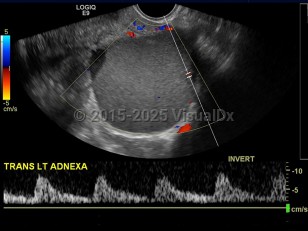

The exact etiology of this condition is unclear, but the prevailing thoughts are toward retrograde menstruation (endometrial fragments pushed into the abdomen through the fallopian tubes) and localized lymphatic spread. Areas affected can include all abdominal organs but most commonly involve the ovaries, bladder, fallopian tubes, and the uterine support ligaments. Less common sites of involvement may include the umbilicus, incisional scars, and the omentum.

Endometriosis affects approximately 6%-10% of women of reproductive age. Presenting symptoms can be nonspecific and variable but may include fatigue, cyclic pelvic pain, pain with intercourse, abdominal pain, chronic pain, painful periods, or pain with bowel movements or a full bladder. This condition can also be completely asymptomatic and only present as infertility (which affects about one-third of patients) or as an incidental finding at the time of an unrelated surgery. It is sometimes associated with somatic mutations in the ARID1A, PIK3CA, KRAS, or PPP2R1A genes.